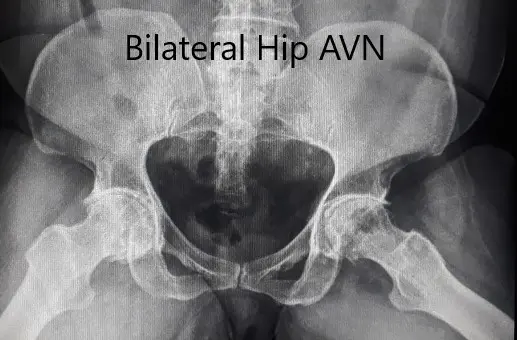

Pre-operative X-ray of the pelvis in frog-legged lateral views.

An X-ray was obtained which suggested a deformed head of femur bilaterally. There were features of arthritis bilaterally with joint space reduction, sclerosis, subchondral cysts, and osteophytes bilaterally.